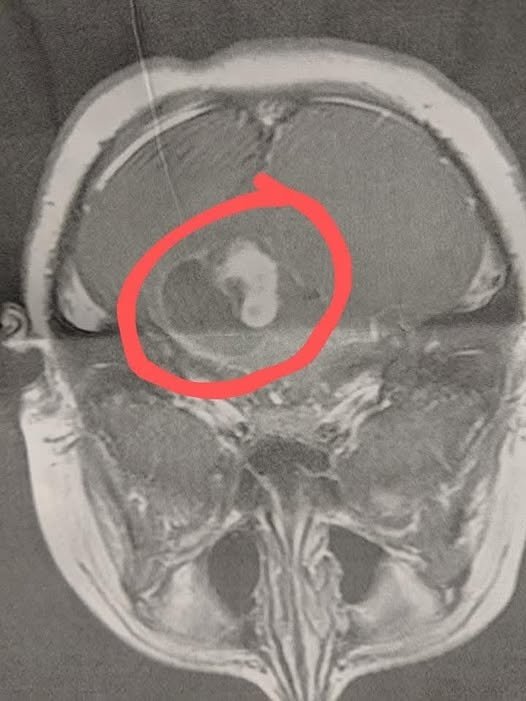

The MRI revealed a large brain tumor with fluid surrounding it. Within hours, my son was rushed to Duke University Hospital for emergency surgery. The operation lasted eight long hours. The surgeon managed to remove 90% of the tumor, but the remaining 10% was too close to the brain stem — too risky to touch.